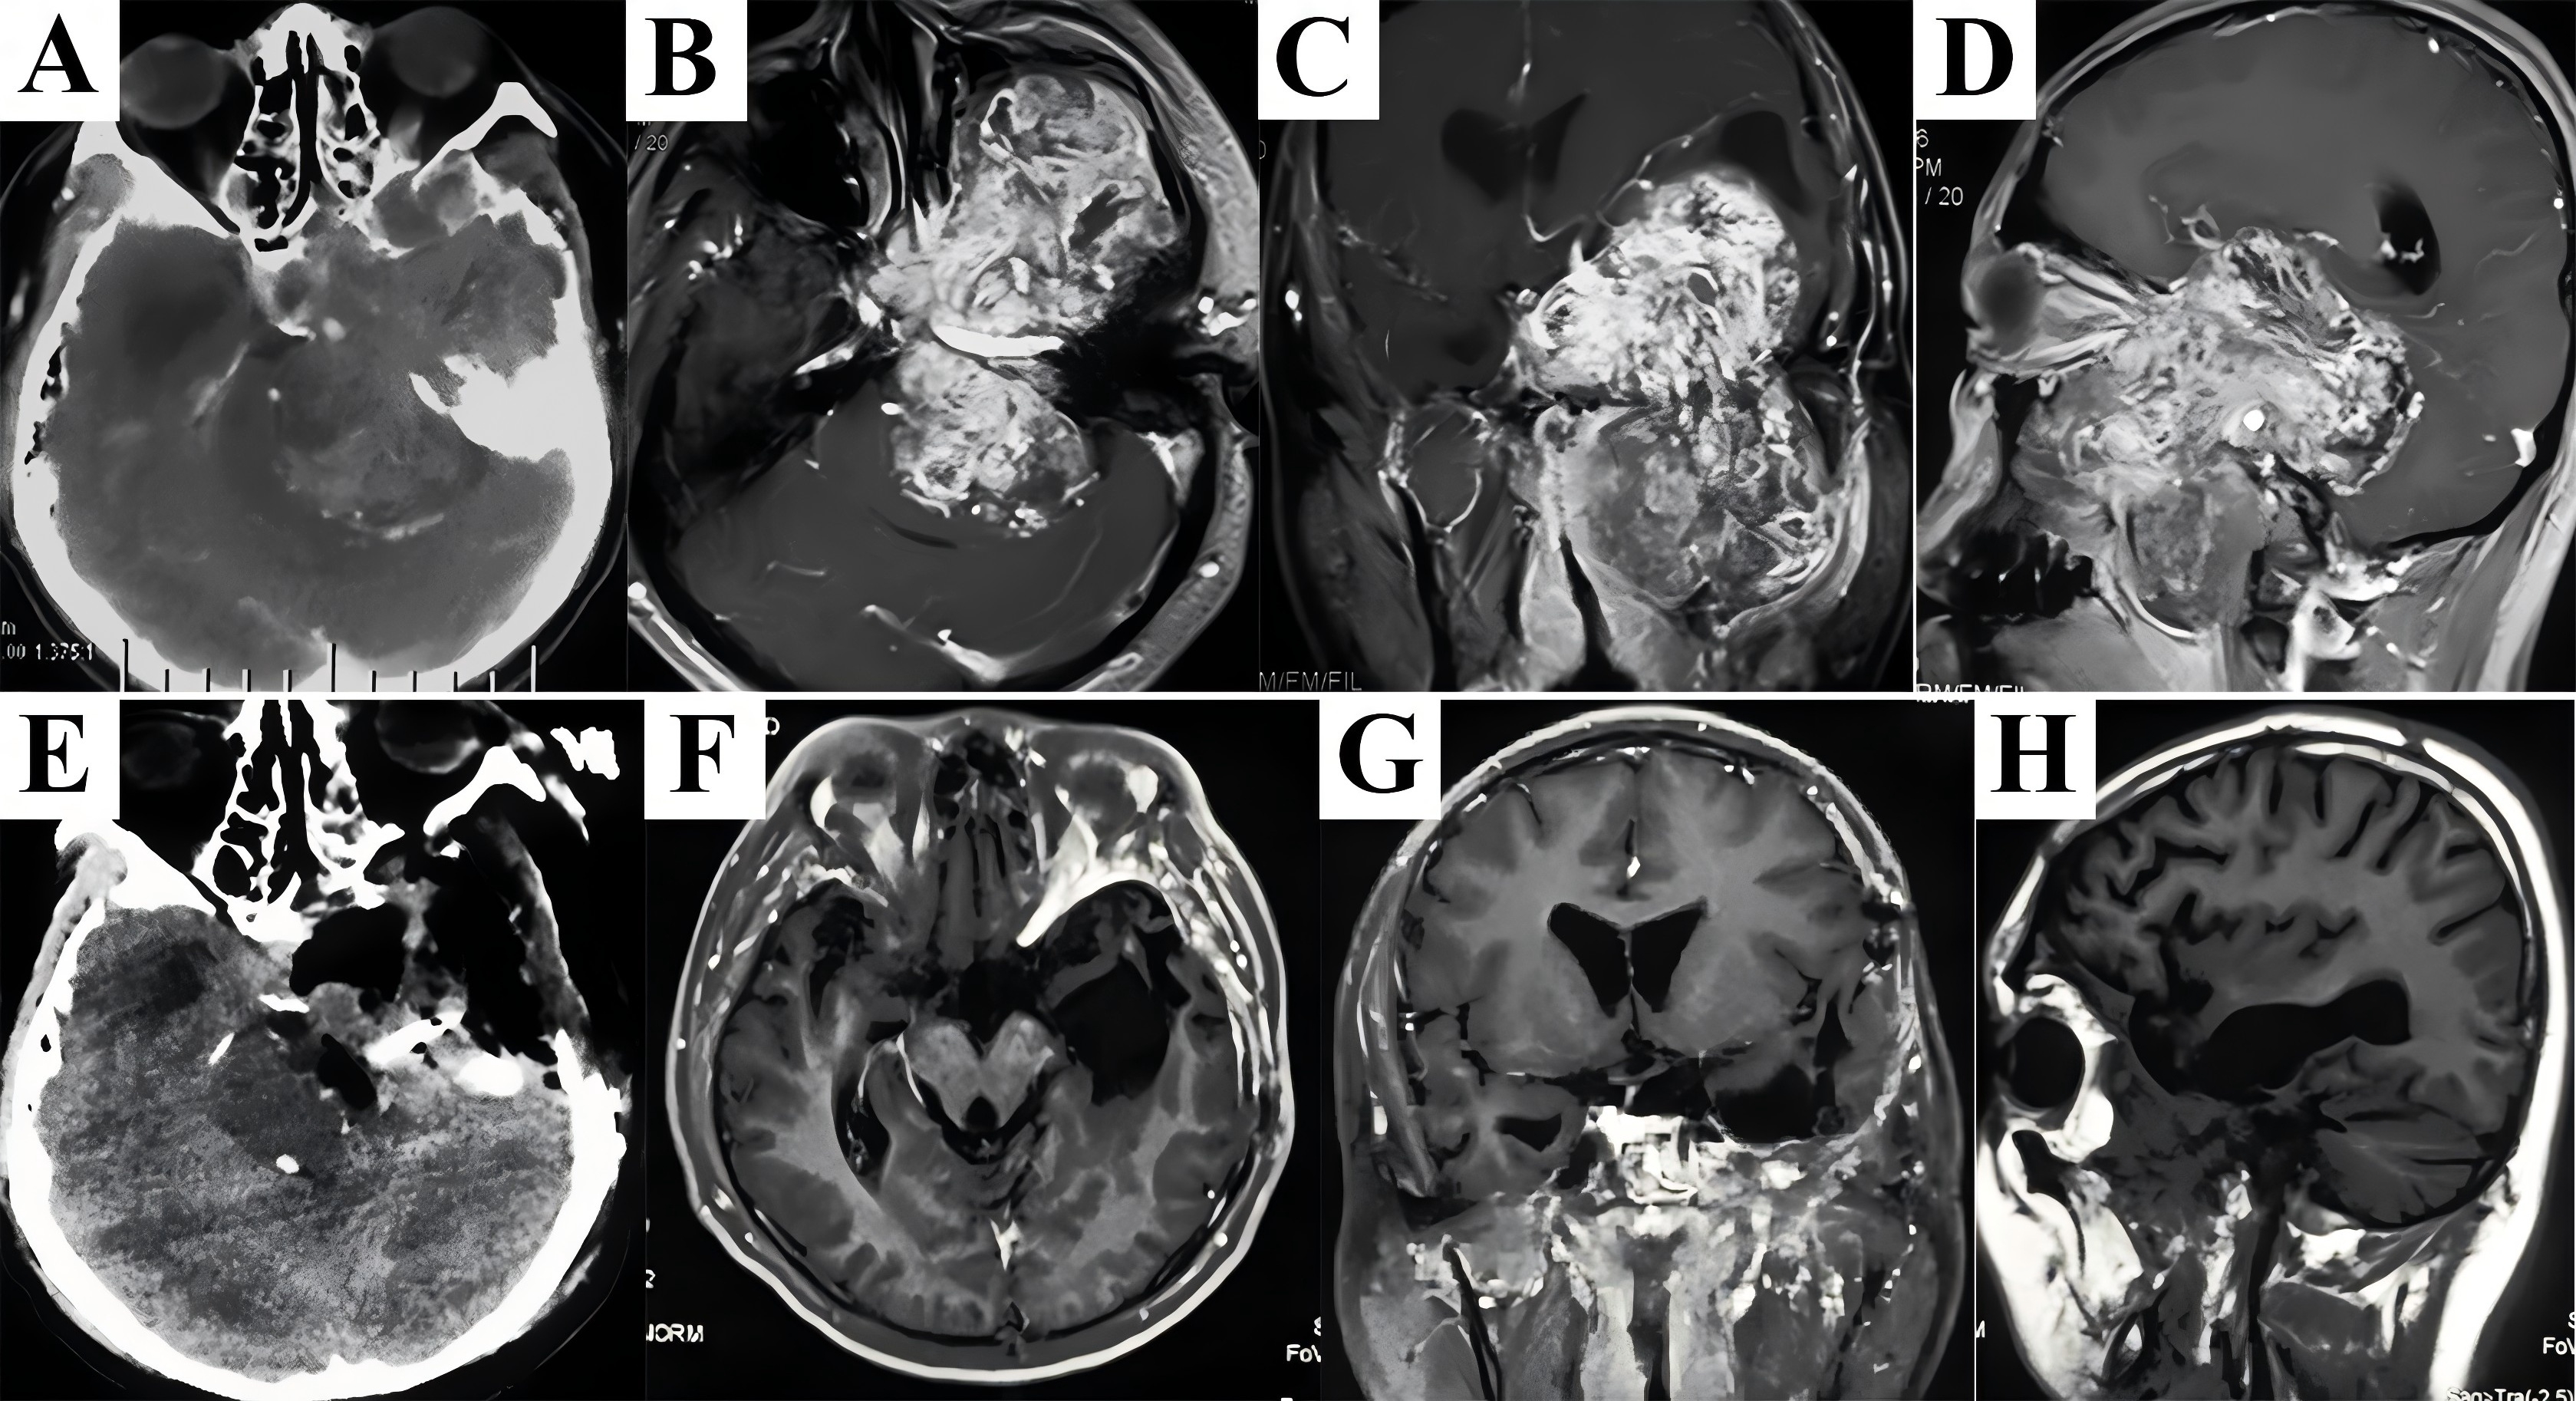

A 29-year-old man initially presented with nasal obstruction and anosmia. Then he complained of blurring 8 months later, and was referred to our clinic because of precipitate bitemporal hemianopsia and severe exophthalmos. Preoperative T2-weighted MRI showed a large lesion with heterogeneous signal intensity in the skull base (Fig. 1A). Contrast enhancement was uneven, which depicted the cystic/necrotic areas within the hypervascularized mass growing inferiorly into the nasal sinuses, anteriorly into the orbits, posteriorly to the sellar, clivus, and petrous apex, bilaterally into the CS, and infiltrating the temporal lobes (Fig. 1B&C). Considering the difficulties in resection of the extensive and calcified lesion in a bloodless view and reconstruction of the skull base through a narrow corridor under endoscopic visualization, the modified maxillary swing approach was selected by expanding nasal osteotomy to the contralateral side. The bony-hard lesion was visualized and dissected along its capsule surface, struggling to keep the displaced and stretched cranial nerves within the CS intact. Pure circumferential stripping in a single piece along the brain-lesion interface was accomplished followed by reflection of frontotemporal scalp flap to harvest malleable autologous tissues for reconstruction (Fig. 1E). Postoperative CT scans confirmed complete removal of the lesion without intracranial hematoma or brain contusion (Fig. 1G). The diagnosis of fibrous dysplasia was finally confirmed by pathological analysis. The postoperative course was uneventful and the patient was discharged with improvement in visual function. He was followed up annually, and no recurrence was seen on contrast T1-weighted MRI (Fig. 1H-J).

Figure 1. Representative case of fibrous dysplasia harboring transdural growth pattern. Heterogeneous signal intensity on plain T2-weighted MRI in axial plane demonstrated an extensive lesion containing cystic/necrotic areas (A). Significantly uneven enhancement seen on T1-weighted post-gadolinium MRI in axial (B) and coronal (C) planes confirmed the hypervascularized lesion infiltrated the brain parenchyma. There was stone-like calcification in the core of the mass which also presented aggressive features of bone destruction on CT scans (D). After adequate exposure of retromaxillary area, complete excision of the lesion was accomplished followed by multilayer reconstruction of the skull base to prevent CSF leakage and obliterate surgical cavity using the temporalis fascia, pericranium, and muscle flap (E). The cosmetic results were acceptable without visible facial scars 3 months after surgery (F). Postoperative CT scans (G) and contrast T1-weighted MRI (H-J) exhibited the excellent outcomes. MRI, magnetic resonance imaging; CT, computed tomography. CSF, cerebrospinal fluid.

InformationFigure 1. Representative case of fibrous dysplasia harboring transdural growth pattern. Heterogeneous signal intensity on plain T2-weighted MRI in axial plane demonstrated an extensive lesion containing cystic/necrotic areas (A). Significantly uneven enhancement seen on T1-weighted post-gadolinium MRI in axial (B) and coronal (C) planes confirmed the hypervascularized lesion infiltrated the brain parenchyma. There was stone-like calcification in the core of the mass which also presented aggressive features of bone destruction on CT scans (D). After adequate exposure of retromaxillary area, complete excision of the lesion was accomplished followed by multilayer reconstruction of the skull base to prevent CSF leakage and obliterate surgical cavity using the temporalis fascia, pericranium, and muscle flap (E). The cosmetic results were acceptable without visible facial scars 3 months after surgery (F). Postoperative CT scans (G) and contrast T1-weighted MRI (H-J) exhibited the excellent outcomes. MRI, magnetic resonance imaging; CT, computed tomography. CSF, cerebrospinal fluid.